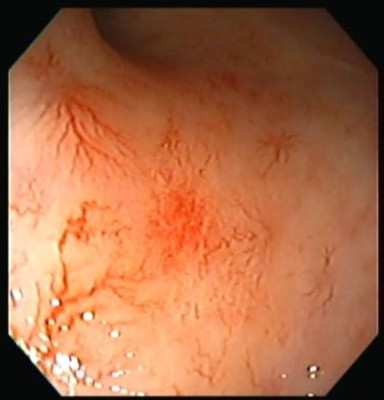

Proctitis

Envíado por Dr. Carlos Ernesto Arévalo